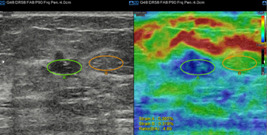

ElastoScan™ (E-Strain)

E-Strain is designed to enable quick and easy calculation of the strain ratio between two regions of interest for day-to-day practice. Simply by setting the two targets, you can receive accurate, consistent results and make informed decisions in many types of diagnostic procedures such as breast, prostate or gynecological examinations.